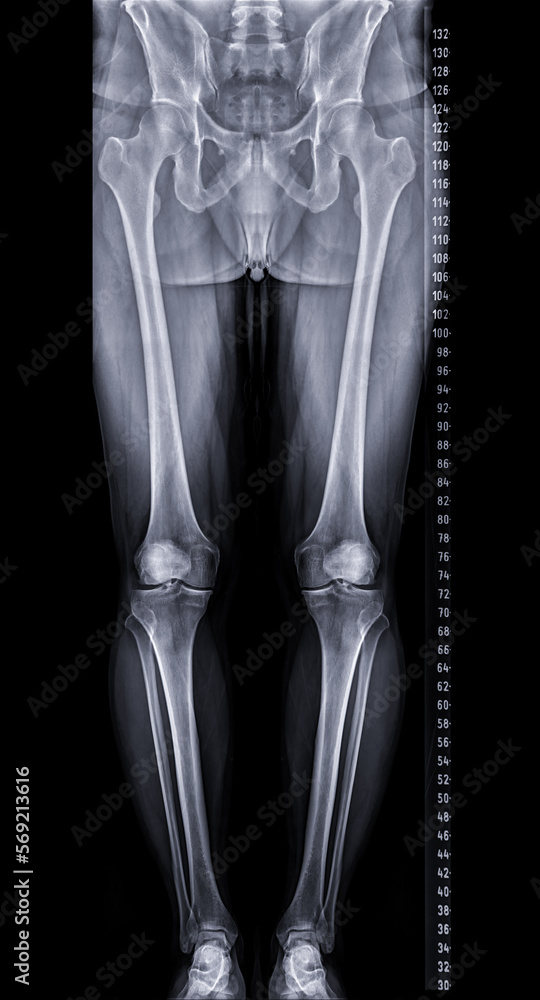

Scanogram or Xray Image of Lower Extremity for Diagnostic Joint What Is A Scanogram X Ray The ct localizer radiograph, also known as scanogram, scout and surview, is the name given to the initial images obtained at the. Radiography provides the most reliable means of obtaining accurate measurements of the length of long bones, specifically length differences between the two. Using the ruler in the images (either directly or for calibration of measuring software), measure the.. What Is A Scanogram X Ray.

Scanogram is a Fulllength standing AP radiograph of both lower What Is A Scanogram X Ray What is a scanogram for leg length? Using the ruler in the images (either directly or for calibration of measuring software), measure the. Radiography provides the most reliable means of obtaining accurate measurements of the length of long bones, specifically length differences between the two. The ct localizer radiograph, also known as scanogram, scout and surview, is the name given. What Is A Scanogram X Ray.